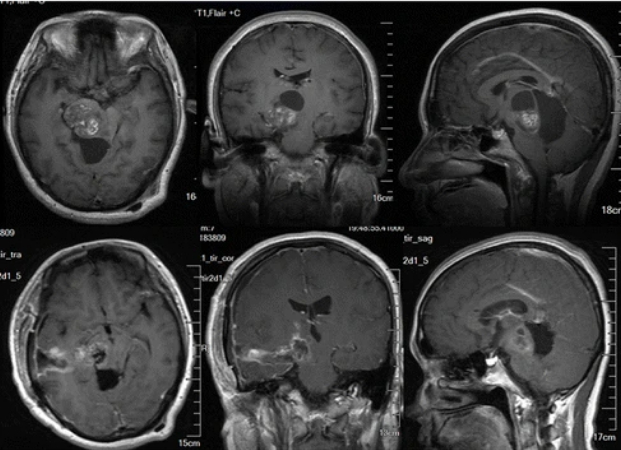

至于丘脑上的肿瘤容易治吗? INC国际神经外科指出,丘脑胶质瘤优选治疗方式便是手术切除,而丘脑胶质瘤位置深在、周围结构复杂,是全部中枢神经系统肿瘤中难度较高的手术之一。以往,在CT和核磁共振,特别是核磁共振问世之前,整个脑胶质瘤手术处于“黑暗时代”,因为无法准确定位。CT和核磁共振的问世大大提高了手术的成功率。

而对于丘脑胶质瘤,由于其不同部位、位置很深,所以在90年代以前,以前由于技术的限制没法做到全切,或者全切后死亡率高。一般都不赞成的手术切除,而是主张做个活检,接下来做放化疗,造成丘脑胶质瘤预后一直不好。随着医学的不断进步,到了90年代,由于显微技术和影像技术等的发展和进步,以及一些新辅助技术的应用,手术成功率和切除率大大提高,手术成了丘脑胶质瘤的优选。特别是在国际神经外科专家的手术下,即使是三级丘脑胶质瘤,也都能得到较好的治疗,比如国际颅底肿瘤手术教授巴特朗菲教授、国际神经外科学院(WANS)主席William T. Couldwell教授、国际神经外联合会(WFNS)颅底手术委员会主席Sebastien Froelich教授、国际神经外科学院院长James T. Rutka教授,他们的胶质瘤手术具有切除率较高、治愈率较高、复发率较低的特点。